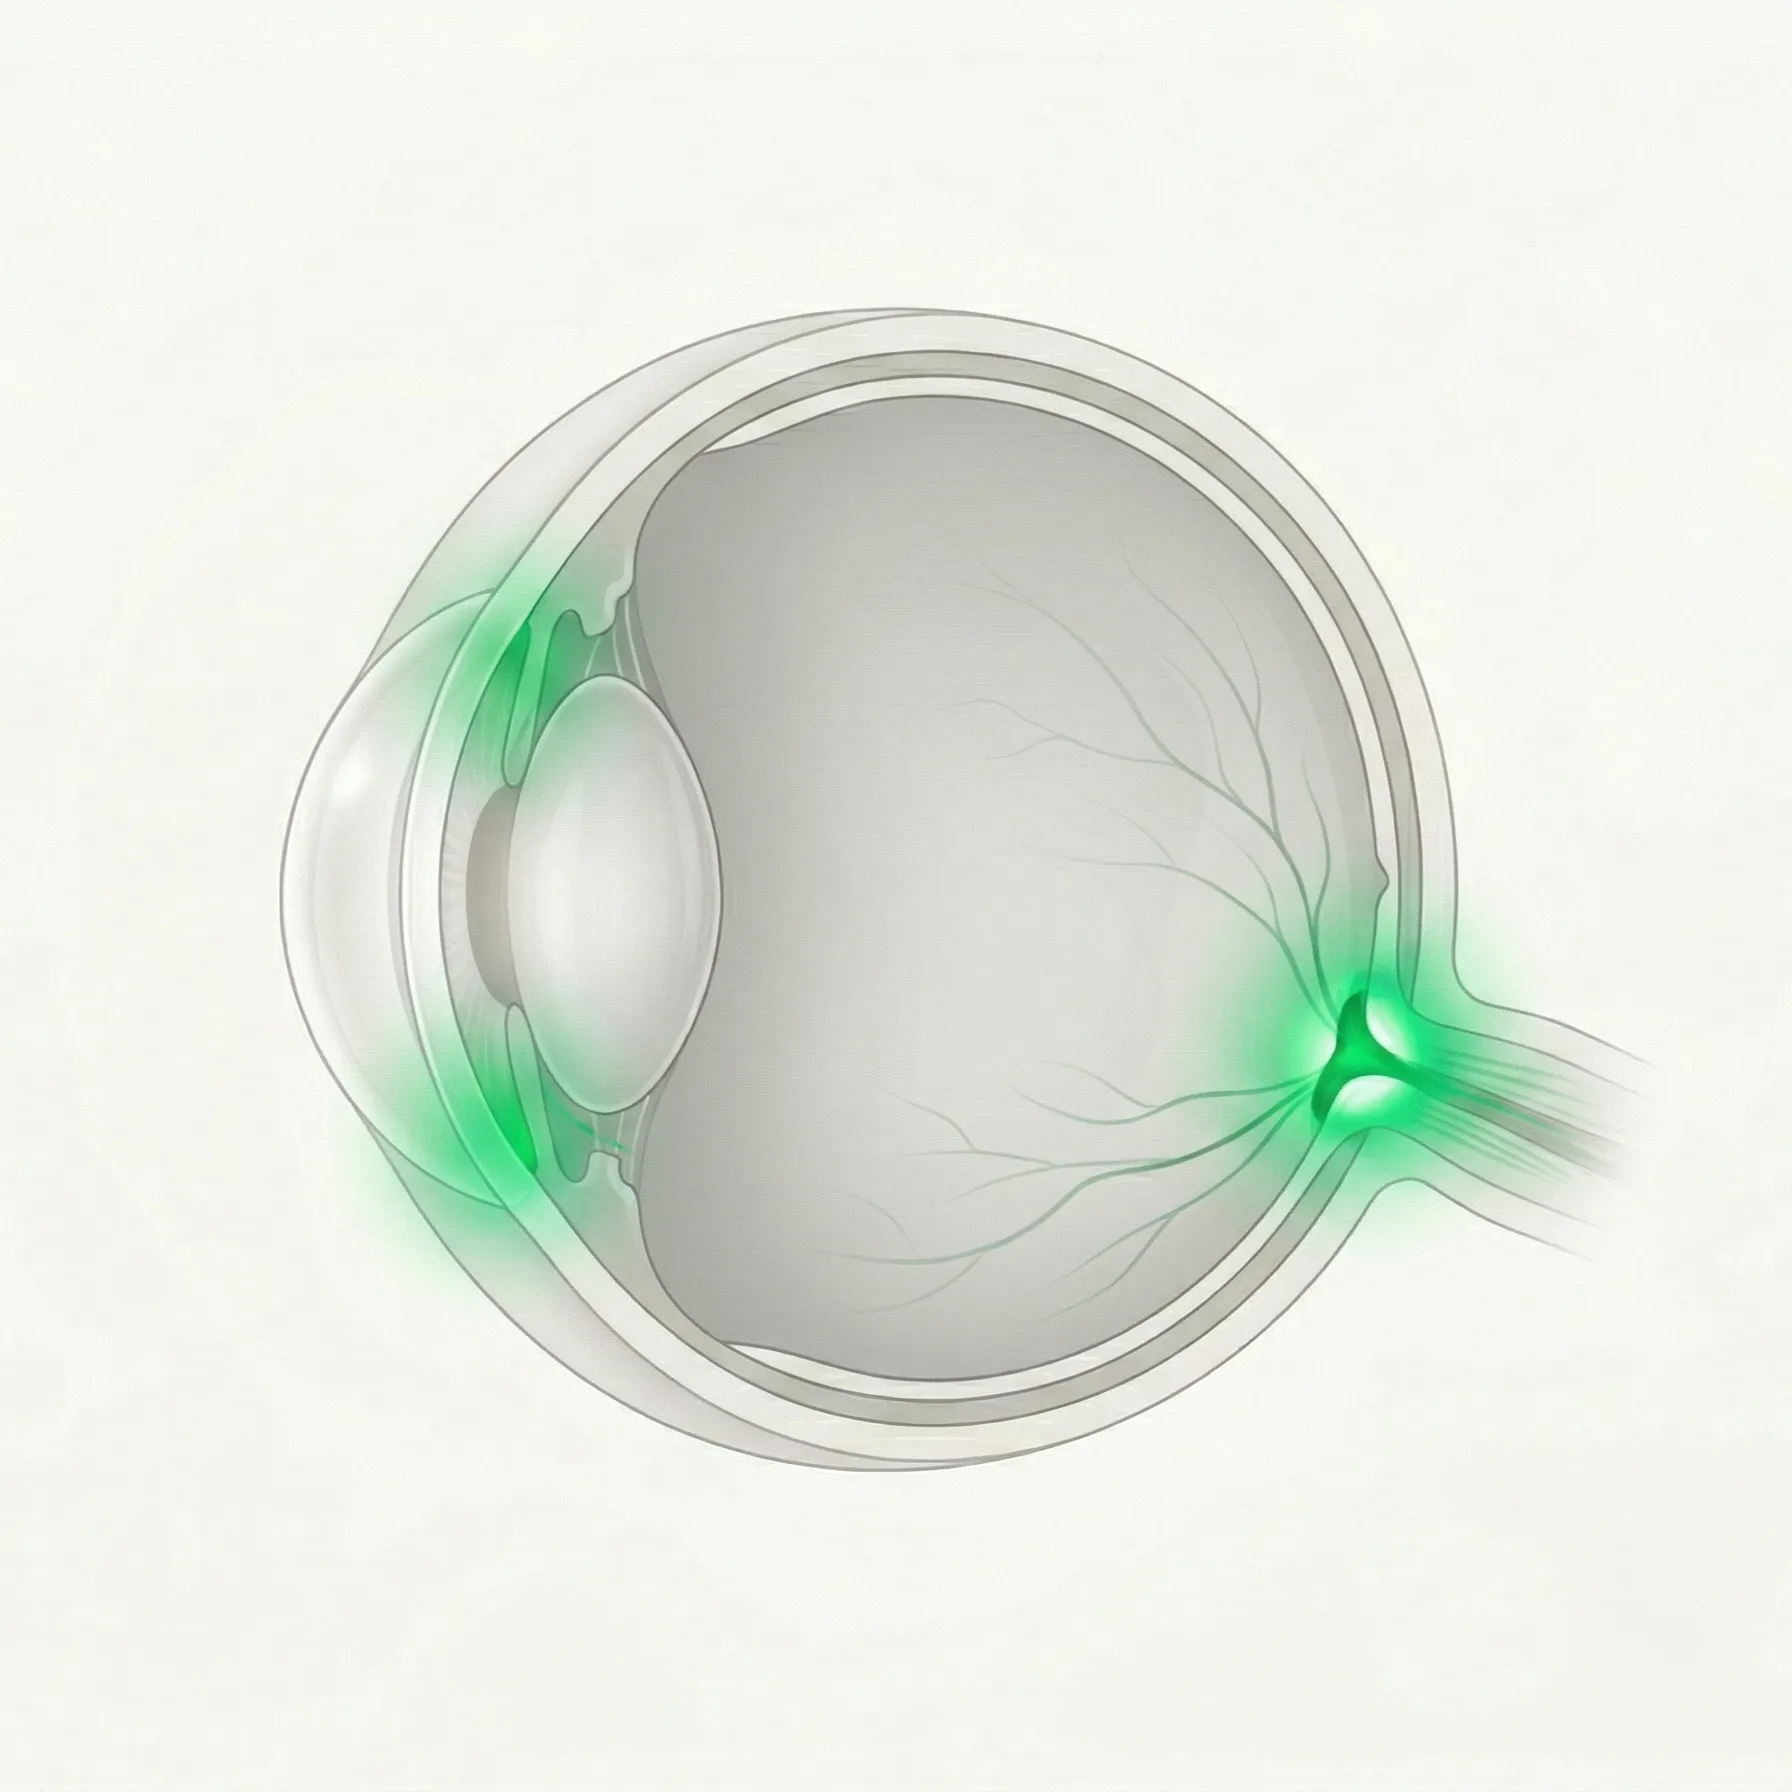

緑内障は、眼圧をはじめとするさまざまな要因によって視神経が進行性に障害され、見える範囲(視野)が狭くなっていく疾患の総称です。このカテゴリでは、隅角の形態や眼圧の値による病型分類と、それぞれの特徴・治療方針を扱います。